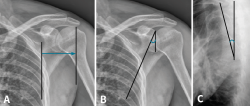

Tras la realización del estudio de imagen obtuvimos unas medidas de 64 mm para el offset del borde lateral, un ángulo glenopolar de 27,5°, una angulación de la deformidad correspondiente a 12,9° (Figura 6) y, por último, una superficie articular conservada íntegramente, visualizada en los cortes y en la reconstrucción tridimensional de la TC.

Figura 6. A: offset del borde lateral; B: ángulo glenopolar; C: angulación de la deformidad.

La reconstrucción tridimensional de la TC se acepta como el método más preciso para visualizar estas lesiones y realizar una mejor evaluación del porcentaje de superficie articular afectada, del offset del borde lateral, de la deformidad angular y del ángulo glenopolar, ya que pueden ser medidos cuantitativamente. Además, una impresión tridimensional permite al cirujano una mejor planificación de la cirugía en cuanto a las maniobras de reducción necesarias y a las medidas del material de osteosíntesis que será requerido para solidarizar los fragmentos fractuarios en el momento de la intervención (Figura 12).